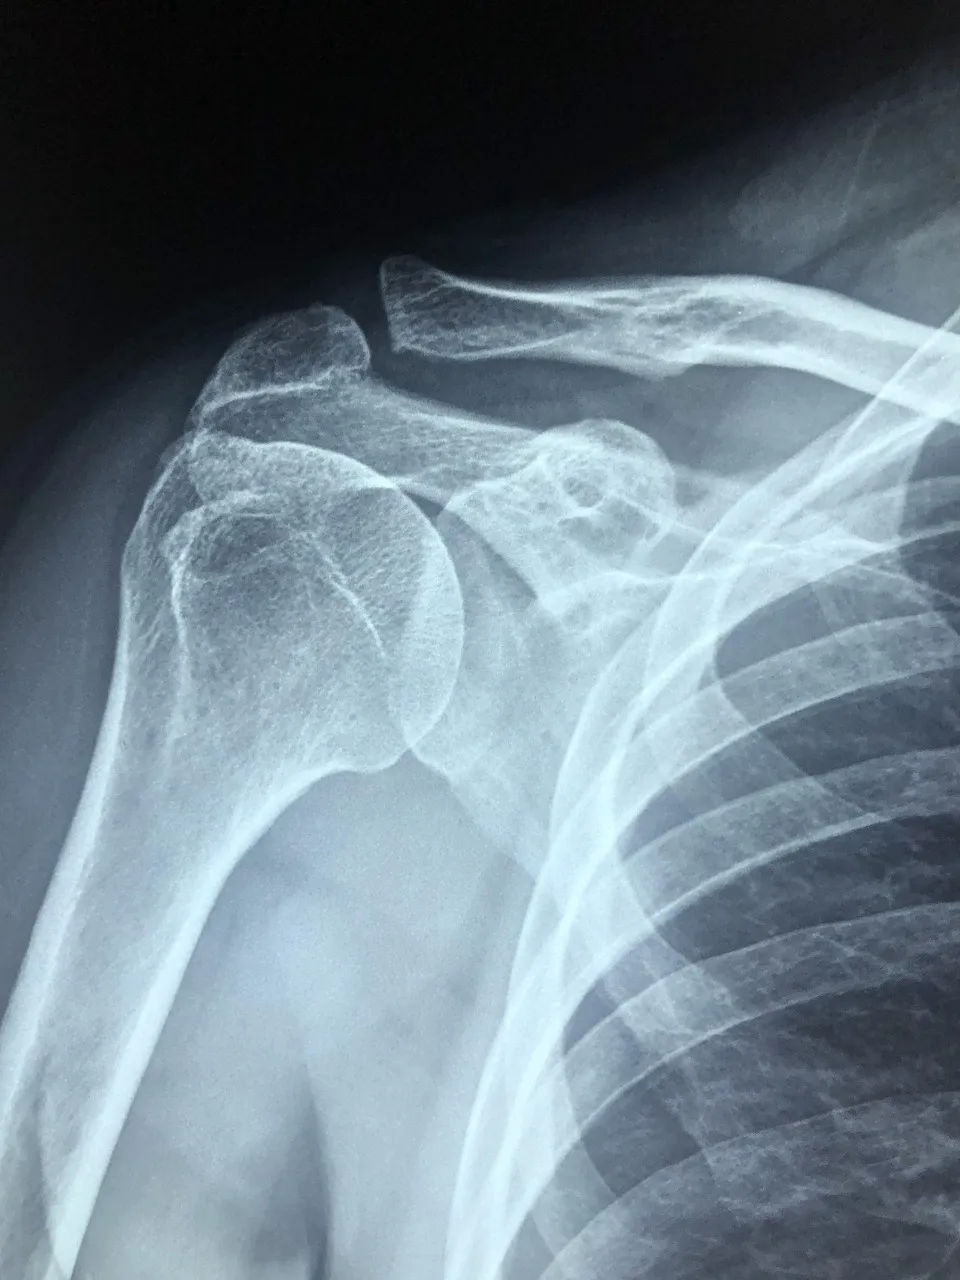

콘드로이친(Chondroitin)은 우리 몸의 연골과 결합조직 속에 자연적으로 존재하는 성분으로

관절 사이에서 충격을 흡수하고 마찰을 줄여주는 역할을 합니다.

나이가 들면서 콘드로이친이 점점 감소하면 관절이 뻣뻣해지고 통증이 생길 수 있다고 합니다.

콘드로이친 효능 2 – 연골 보호 및 재생 도움

콘드로이친은 단순히 통증을 완화하는 것에 그치지 않고,

-연골 세포의 손상을 줄이고 재생을 돕는 역할도 합니다.-

콘드로이친 효능 3 – 관절 윤활 및 유연성 개선

콘드로이친은 관절 속의 윤활 작용을 촉진해 마찰을 줄여주는 역할을 합니다.

실제로 콘드로이친은 관절액의 점도를 높여 유연성을 개선하는 효과가 있다고 합니다.